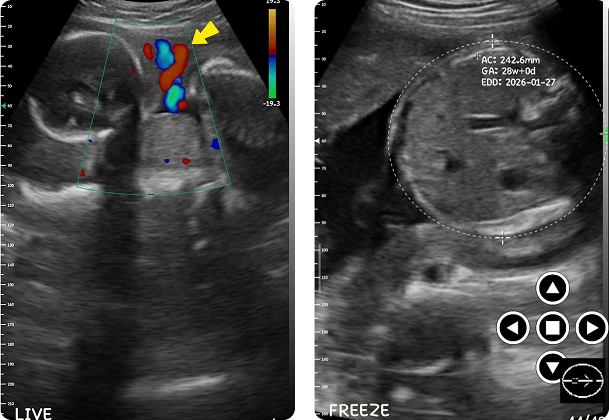

La ecografía durante el embarazo resulta muy valiosa en este caso. Las madres y sus médicos pueden seguir con seguridad el desarrollo del bebé a lo largo de los meses de gestación.

Las ecografías del embarazo pueden revelar: